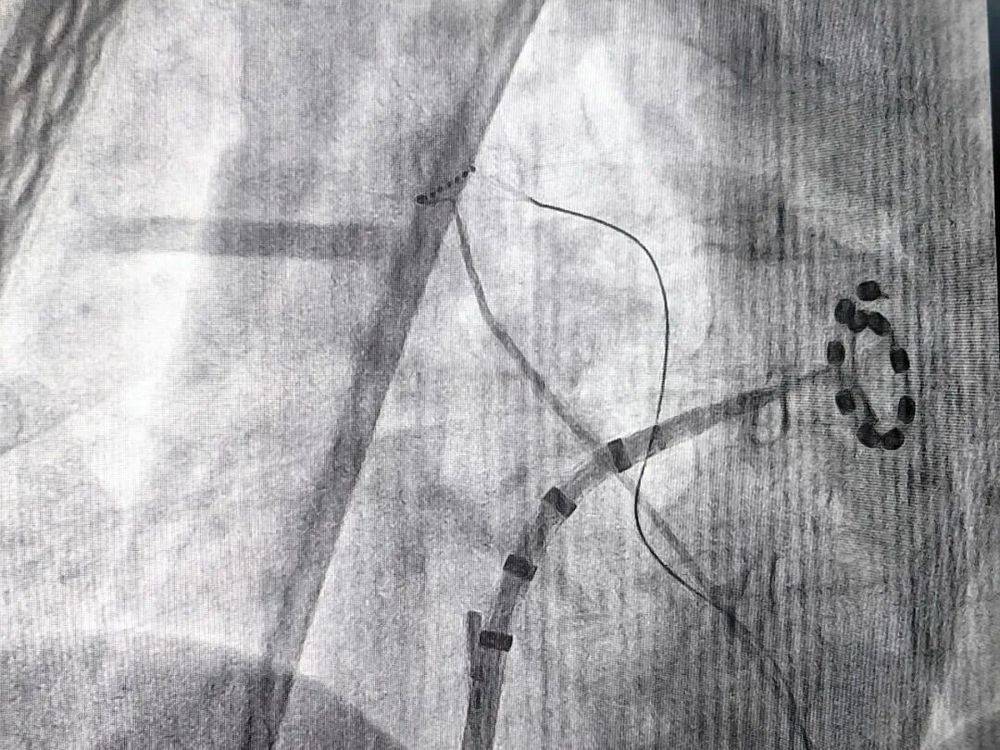

三维脉冲房颤手术影象图 (李新芳 摄)